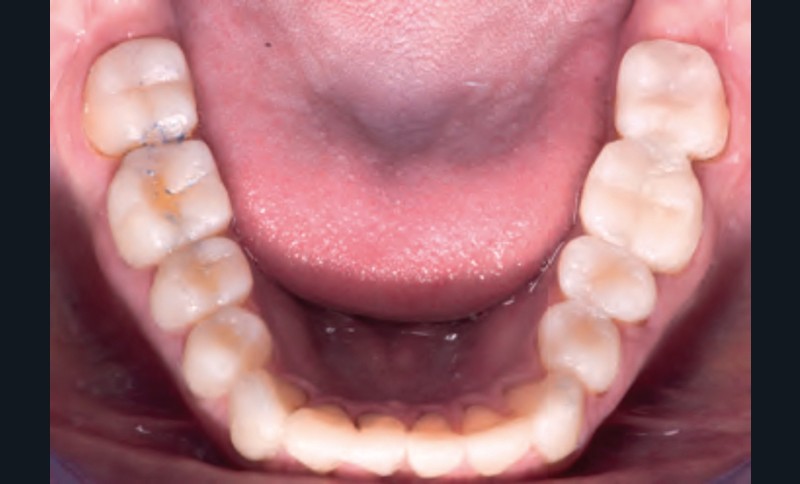

Jean-Pierre Attal : Tout à fait. Mais il faudra donner au prothésiste un maximum d’indications pour qu’il puisse réaliser sa cire de diagnostic. Vous découvrirez que la première étape de la réalisation de ces « full mock-up » est la réalisation d’un projet esthétique virtuel [8] à partir de cadrages photographiques précis aux trois échelles (visage, sourire, dento-gingivale). Gil Tirlet nous expliquera tout cela en détail avec des vidéos que j’ai déjà visionnées et qui sont très impressionnantes (fig. 1 à 4) !

Jean-Pierre Attal : Exactement, car il est possible d’appliquer le protocole de la technique « 3 steps » aux patients présentant des pertes de substance d’origine attritive (bruxisme) (fig. 5).